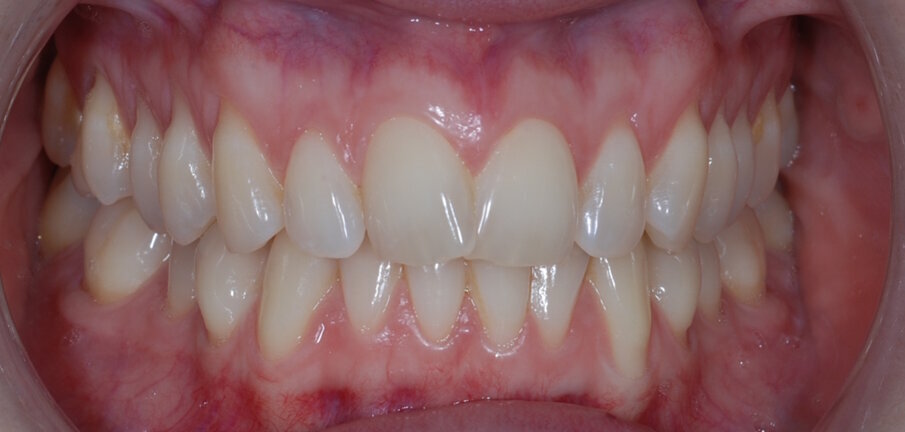

Fig. 15: Post treatment anterior

The patient was very satisfied with the results, especially the fact I was able to improve her smile without affecting the integrity of the enamel. I sent before and after images to the patient at the end of her treatment pathway so that she could see the difference, and she was amazed at how much the aesthetics of her teeth had changed. I was also very happy with the outcome – with the help of the IAS Academy and digital planning tools, treatment was safe and predictable.